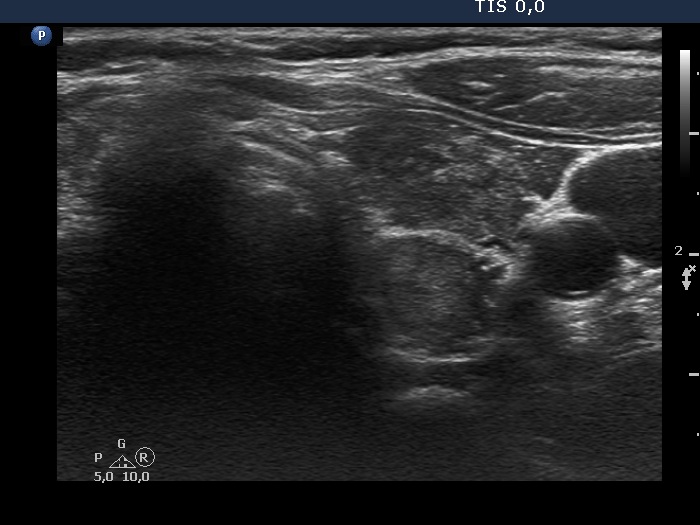

Discrete lesion or nodule in Hashimoto's thyroiditis - case 23 (1401) (ultrasonographic picture 4)

Left lobe, transverse view. There is a thick, linear echogenic bundle in the central part of the lobe which makes the appearance of the dorsal part nodular.